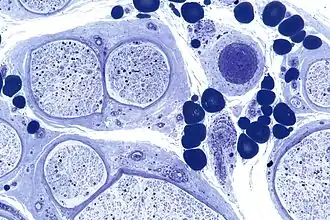

![]() Микрофотография полиневрита при васкулите. Залито пластиком. Толуидиновый голубой. | |

![Микрофотография полиневрита при васкулите. Залито пластиком. Толуидиновый голубой[англ.].](./Vasculitic_neuropathy_-_plastics_-_intermed_mag.jpg)